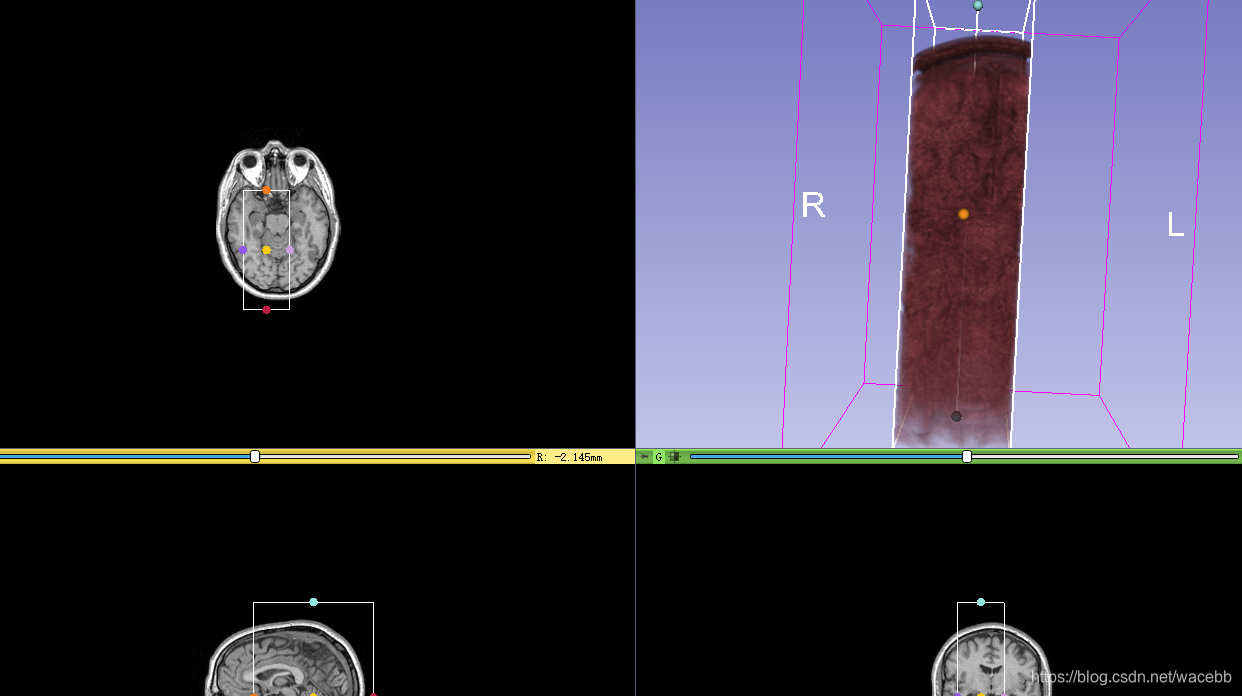

于此同时右边显示界面会展示出ROI框:

然后,我们通过移动ROI点就可以修改ROI区域,同时3D显示出ROI区域: